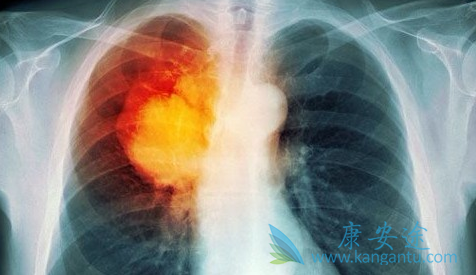

今天看到一条消息,声称分子靶向药物凯美纳(盐酸埃克替尼)在晚期肺癌治疗中可以取代化疗。这是宣传作用还是真的呢?相信很多患者都蒙圈了。凯美纳的主要成分是盐酸埃克替尼,针对的是晚期不能手术的非小细胞肺癌,是国内自主研发的靶向药,确实给很多患者带来了希望。但凯美纳是否能代替化疗,还不能一概而论,患者的情况不同,有的情况复杂,是需要医生综合判断哪一种更适合。

那么哪种情况下,选择凯美纳(埃克替尼)是最好的?靶向药物,顾名思义,是找准肿瘤,像对准靶子一样攻击肿瘤细胞,而不伤害正常细胞。那么凯美纳就能找出EGFR突变类型的非小细胞肺癌肿瘤,对准攻击,对于不是这类型的肿瘤,效果可能不明显,所以一般在用这类靶向药之前,要做一个基因突变检测,看看是不是适合用。如果不做基因检测直接用,都属于盲试。